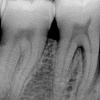

Algav hambanärvi põletik

Algav hambanärvi põletik ehk pöörduv pulpiit on tavaline hambakaariese tüsistus, kui hambaauku põhjustanud mikroobide toksiinid on kahjustamas hambasäsi. Põletik on organismi kaitsereaktsioon ja valu selle üks näht.